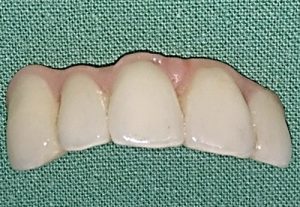

3. PHASE – prosthetic fabrication of temporary crown on implant

3. PHASE – fabrication of temporary solution